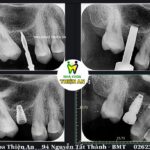

Nâng xoang, ghép xương và trồng 2 implant thay thế răng mất cho c G. (30 tuổi). Tình trạng trước điều trị: vùng xương mất răng hàm trên còn lại ít do mất răng đã lâu, xương tiêu nhiều…

Nâng xoang kín là gì? Là phương pháp tăng chiều cao xương vùng cấy ghép khi xương còn lại quá ít, đây là phương pháp nâng xoang từ bên trong, qua lỗ cấy Implant và không yêu cầu phẫu thuật quá nhiều. Bác sĩ sẽ mở một đường rạch trên nướu đến vùng xoang hàm cần nâng. Sau đó sẽ tạo một lỗ nhỏ ở phần xương để nâng màng xoang lên. Xương hàm cần cấy ghép sau đó sẽ được đưa vào lấp đầy khoảng trống giữa xương hàm và màng xoang mới nâng

Kỹ thuật này ít xâm lấn nên hạn chế sưng đau và đi kèm với quá trình cấy trụ Implant